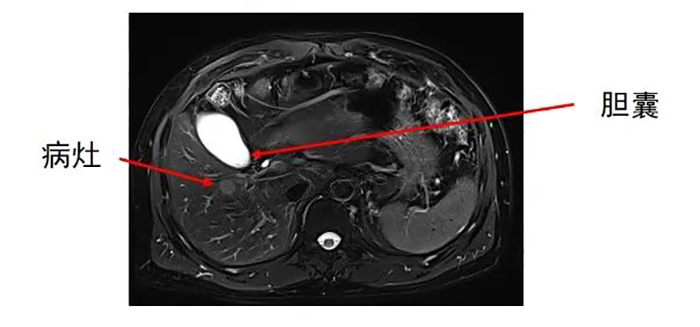

肝内转移灶数目为两个,分别位于左叶和右叶。

齐先生病灶临近大血管、重要脏器。跳蛋视频 专家团队在CT引导下精准定位,经皮穿刺将微波消融针准确置入齐先生肝脏肿瘤部位,然后利用微波能量,使肿瘤组织内的水分子快速振动、摩擦产生热量,从而使局部温度迅速升高,让肿瘤细胞凝固性坏死。整个手术过程顺利,避免了严重并发症发生。

准确插入到病灶内,并避开了门静脉左支及分支,避免了出血并发症。

准确插入到病灶内,并避开了门静脉右支及胆,避免了出血、损伤胆囊等并发症。